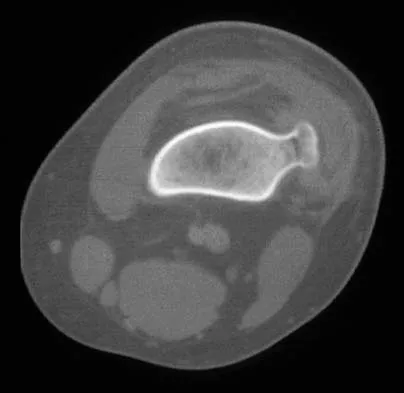

A 30-year-old woman has pain in her right hand. The radiograph, CT scan, and biopsy specimen are seen in Figures 38a through 38c. What is the most likely diagnosis?